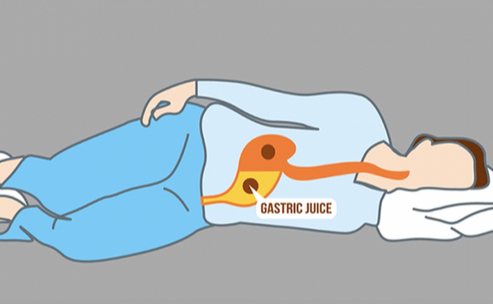

Lying on the examination table, I stared at the ceiling, trying to control my breathing. The room was cool, the gel cold against my skin, and the machine hummed softly in the background. My thoughts raced ahead—treatment, recovery, what life would look like next. I told myself I was prepared for whatever they found.

The technician’s movements began to slow. Her focus shifted, and her expression changed. She leaned closer to the screen, studying it carefully. The silence stretched longer than it should have, and I felt my heartbeat pounding in my chest.

“There’s a heartbeat,” she said quietly.

For a moment, I couldn’t understand what she meant. The words didn’t connect. Then she gently turned the monitor toward me.

And I saw it.

A tiny flicker. Steady. Alive.